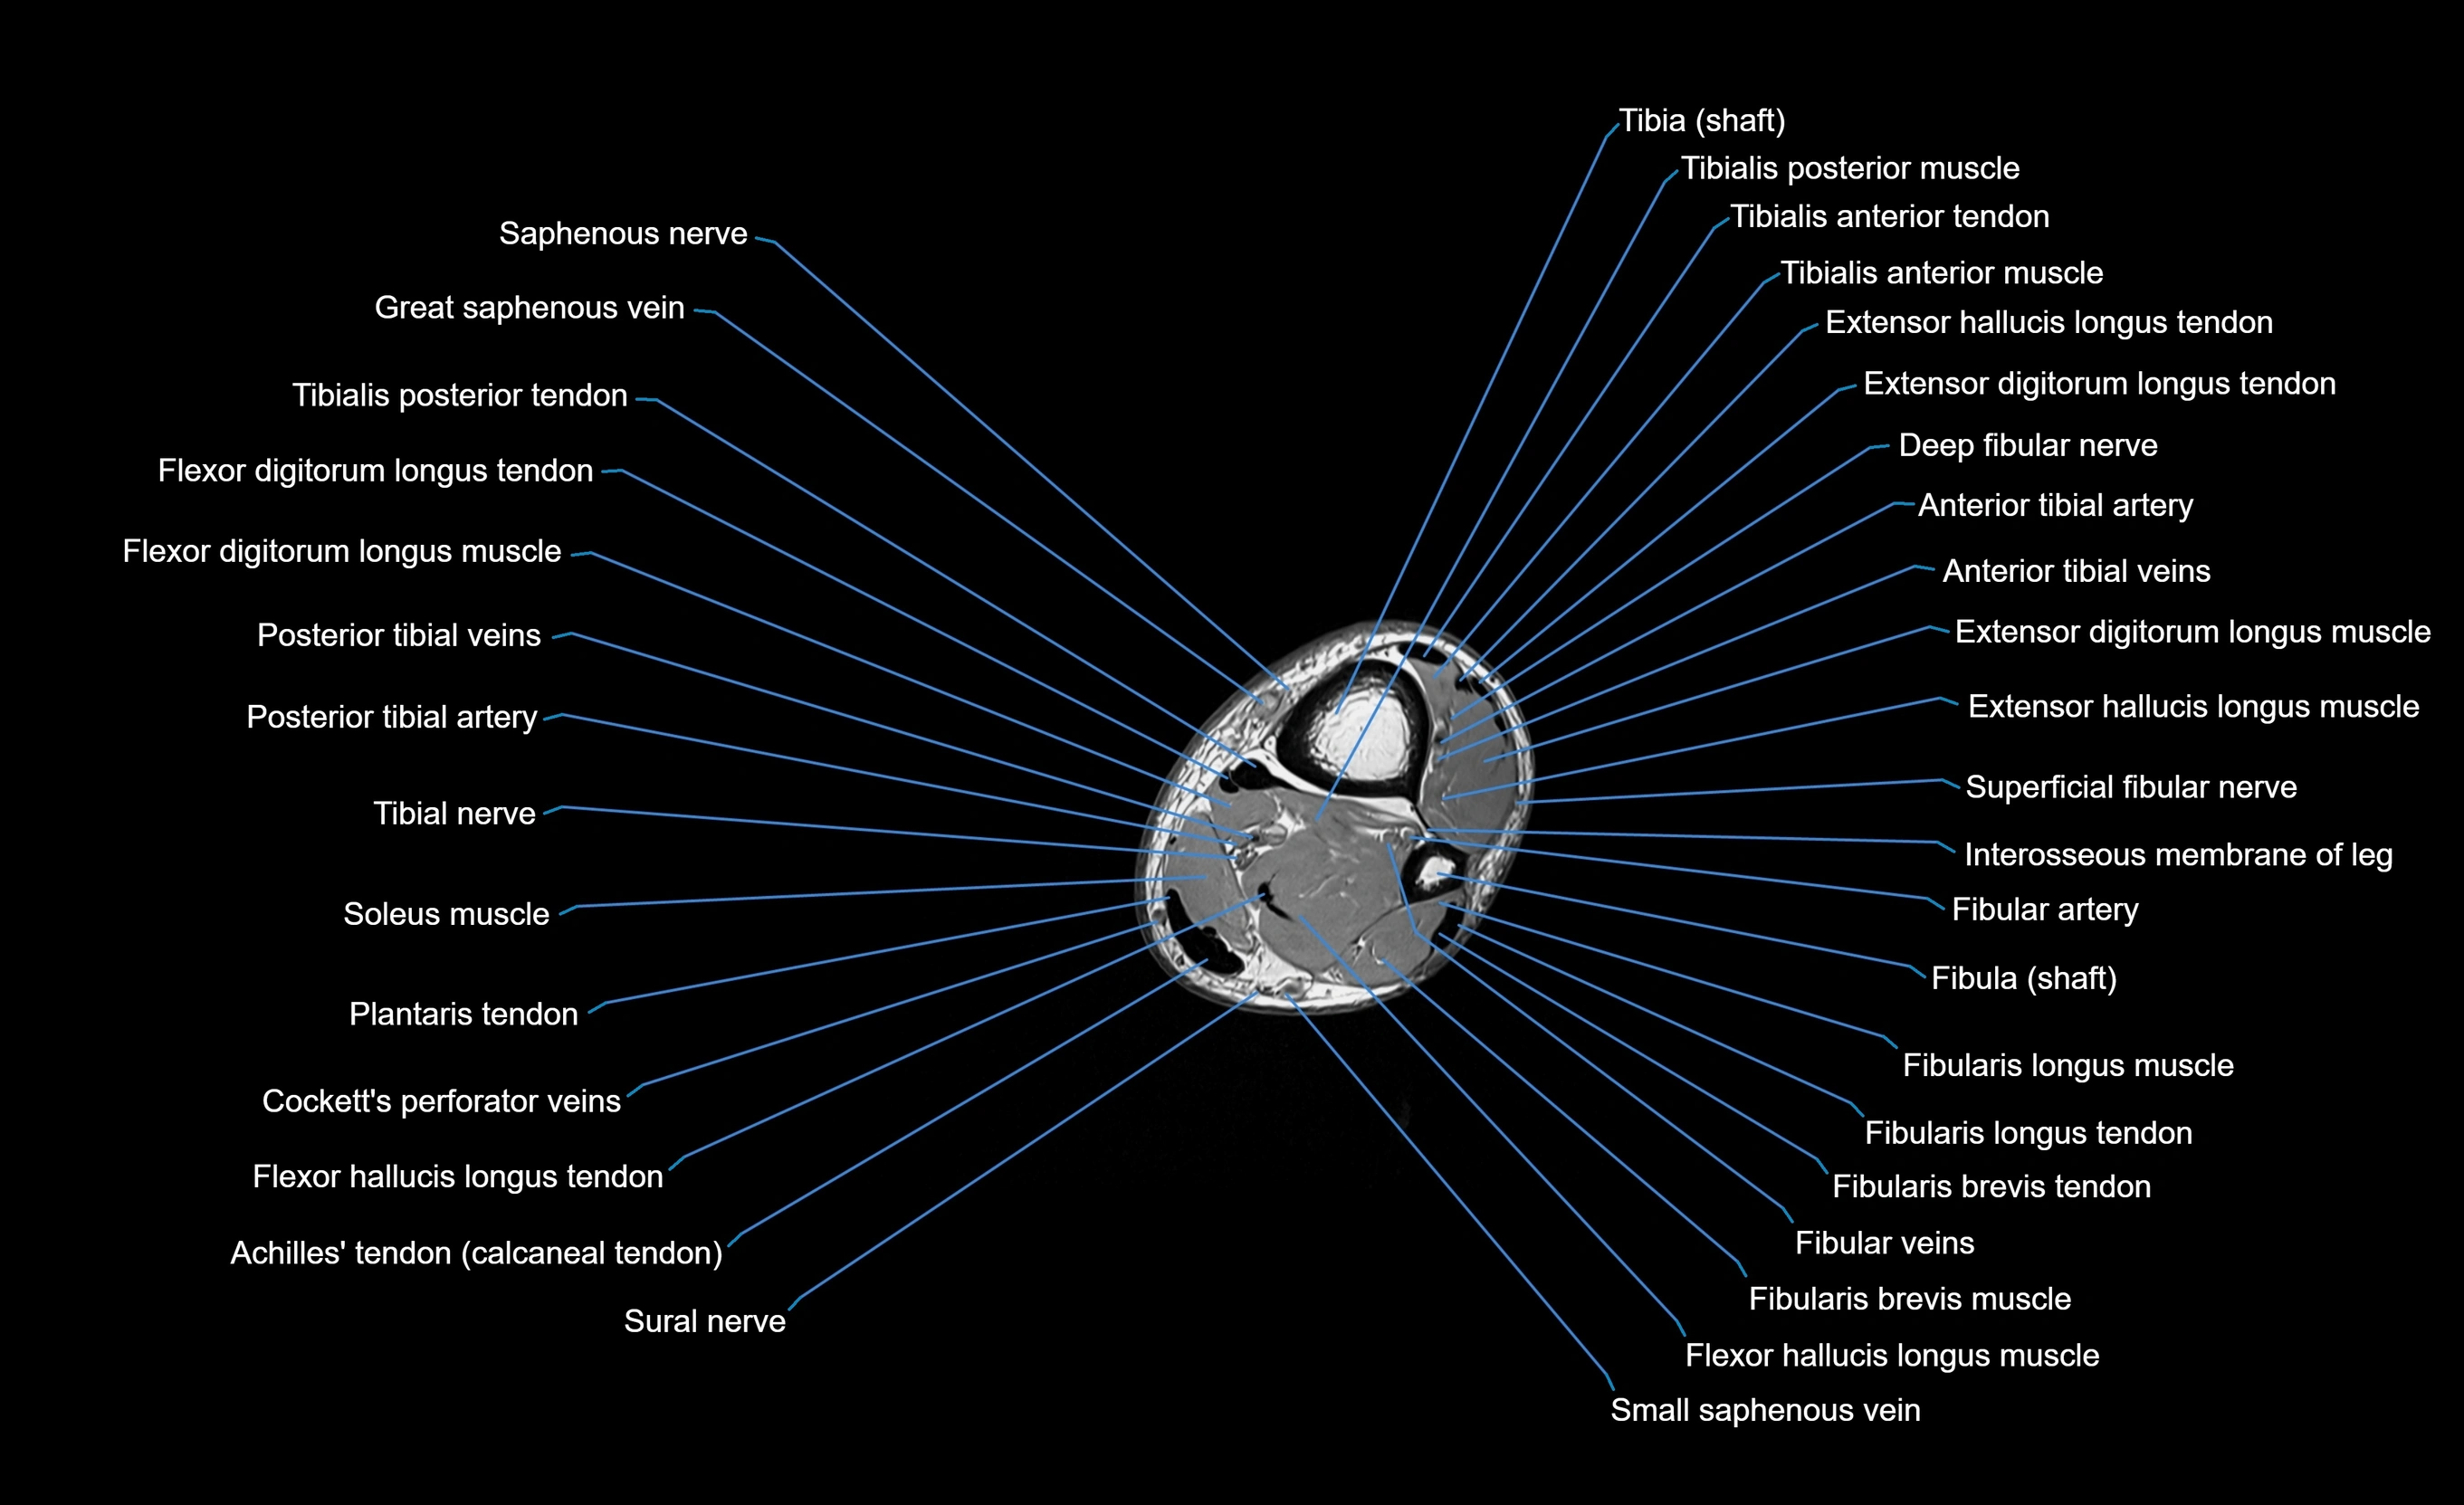

MRI image